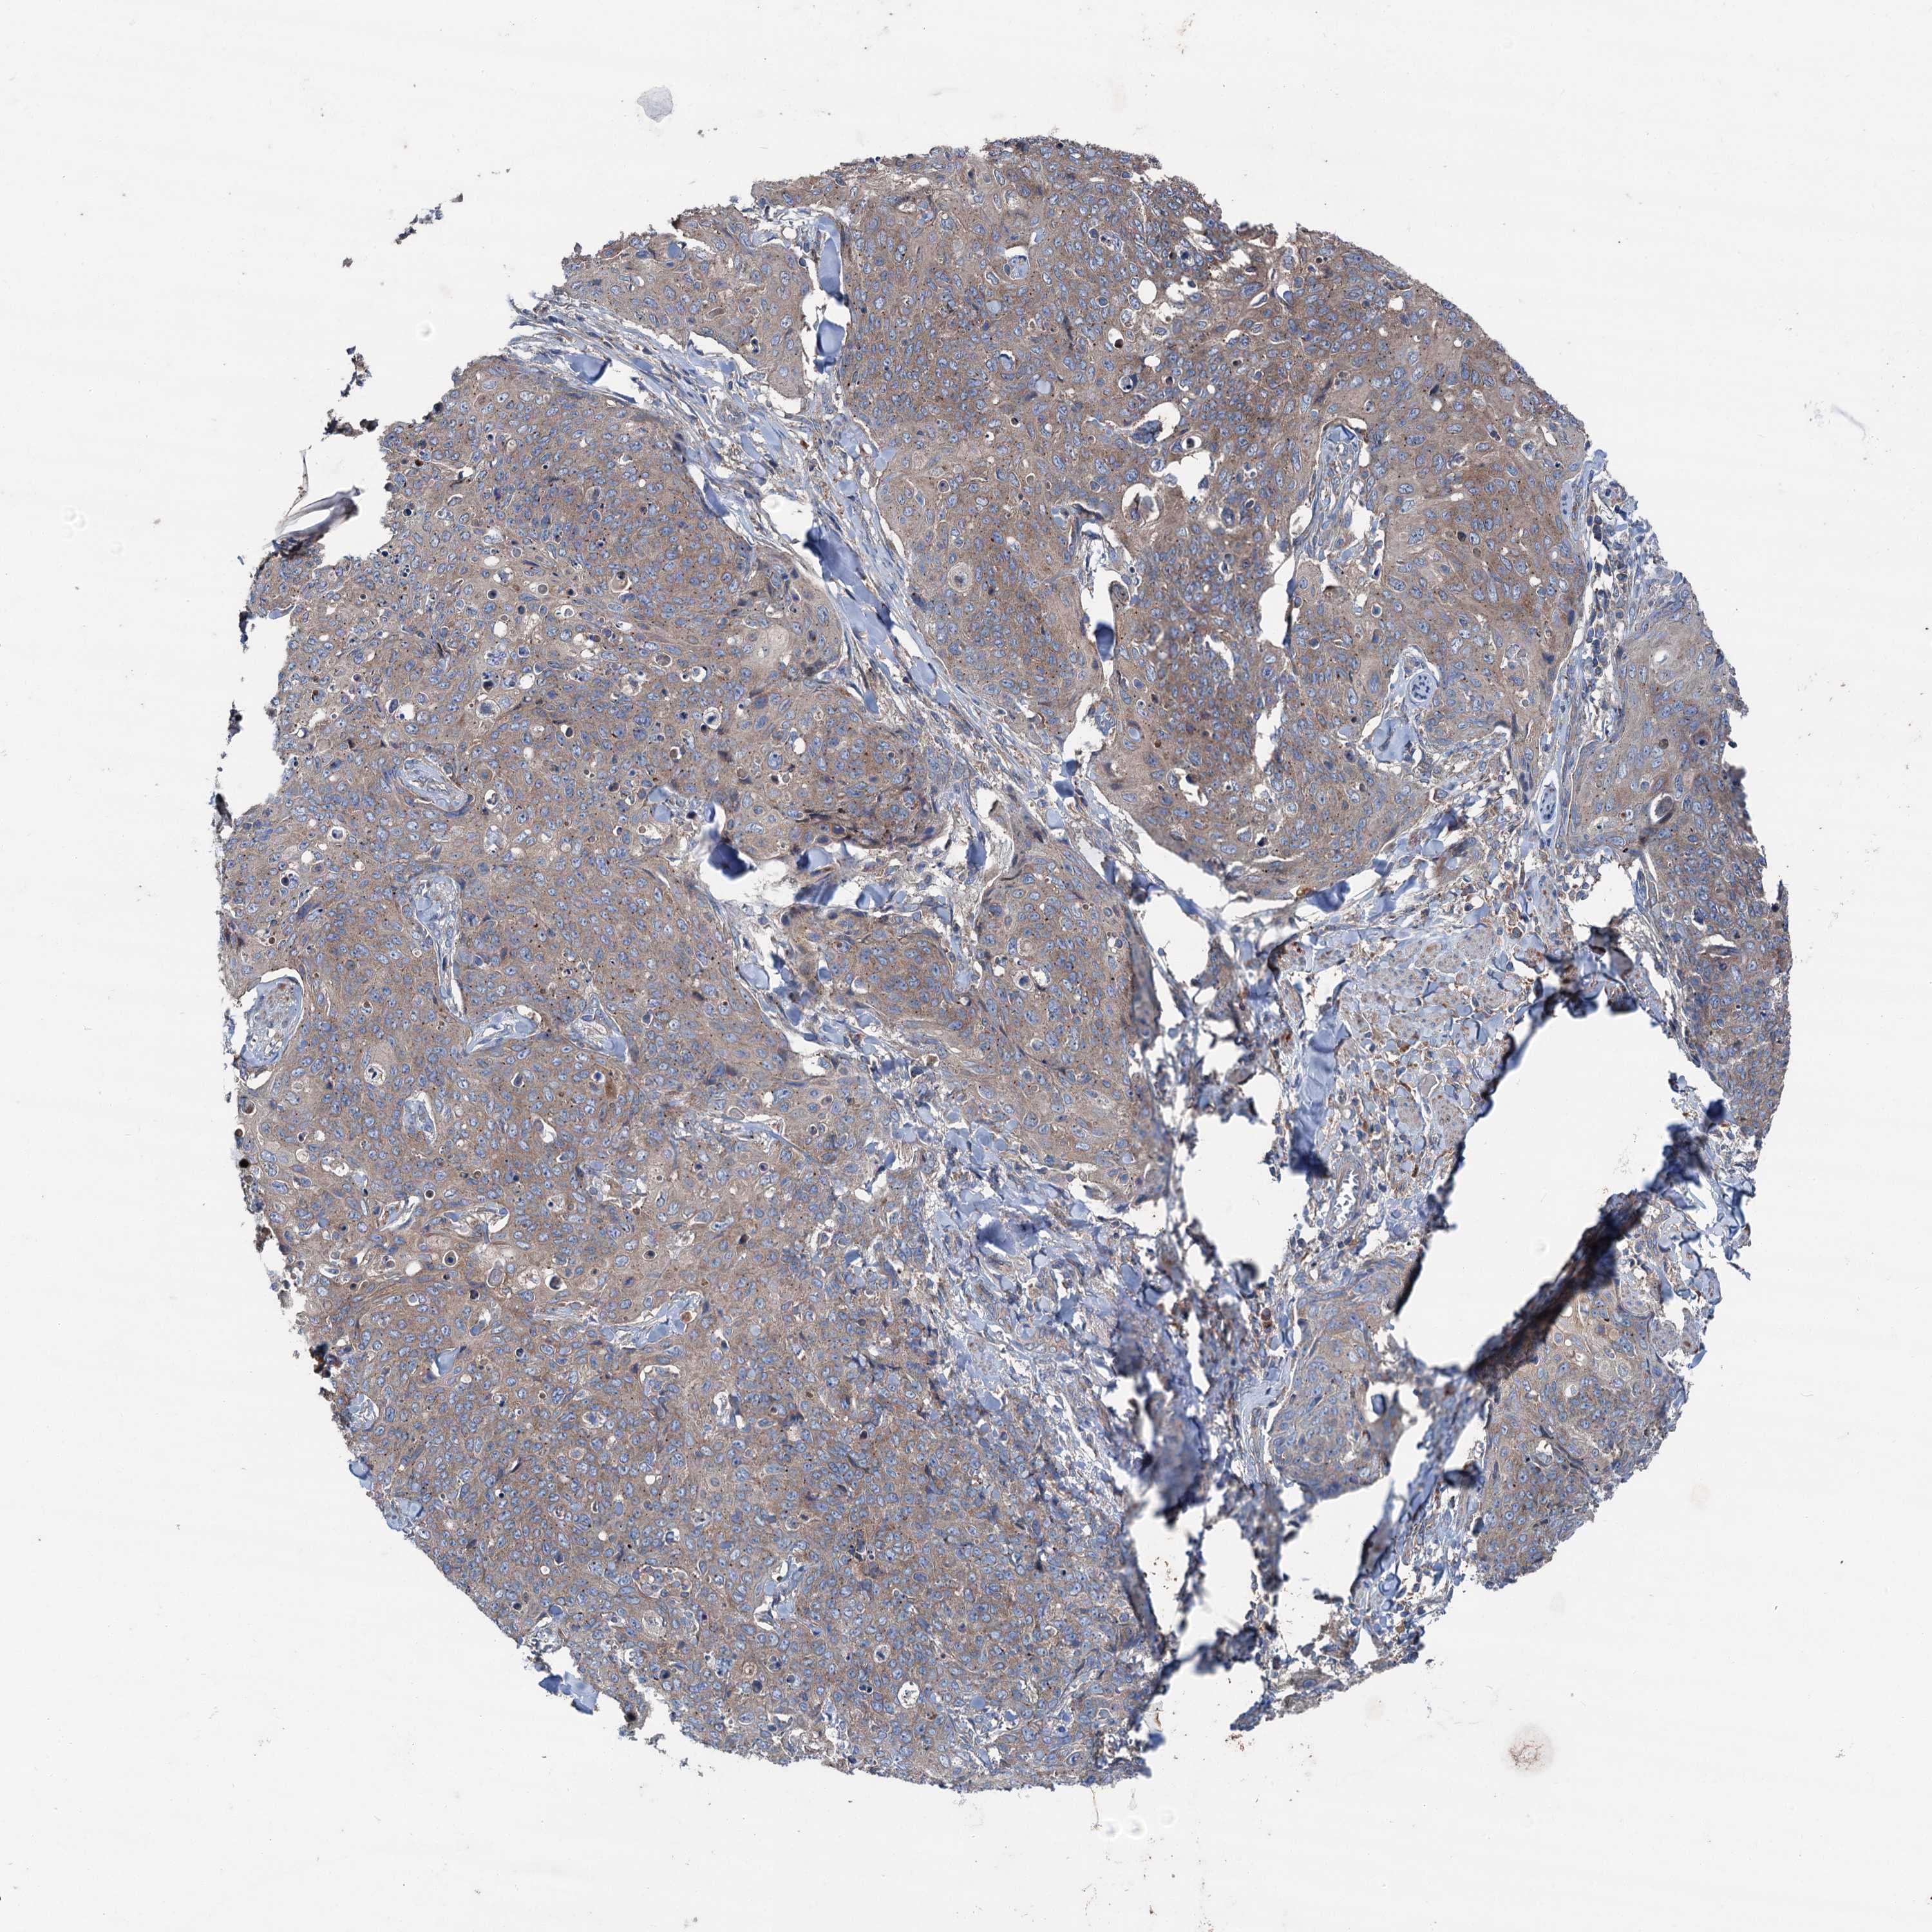

SKIN CANCER - Protein expressioni

A mouse-over function shows sample information and annotation data. Click on an image to view it in a full screen mode. Samples can be filtered based on level of antibody staining by selecting one or several of the following categories: high, medium, low and not detected. The assay and annotation is described here.

Each image is clickable and will lead to virtual microscopy that enables deeper exploration of all samples and also displays staining intensity scores, fraction scores and subcellular localization as well as patient and tissue information for each sample.

Antibody HPA038804

Staining

High

Medium

Low

Not detected

Intensity

Strong

Moderate

Weak

Negative

Quantity

>75%

75%-25%

<25%

None

Location

Nuclear

Cytoplasmic/membranous

Cytoplasmic/membranous,nuclear

Basal cell carcinoma

Squamous cell carcinoma, NOS

Squamous cell carcinoma, metastatic, NOS